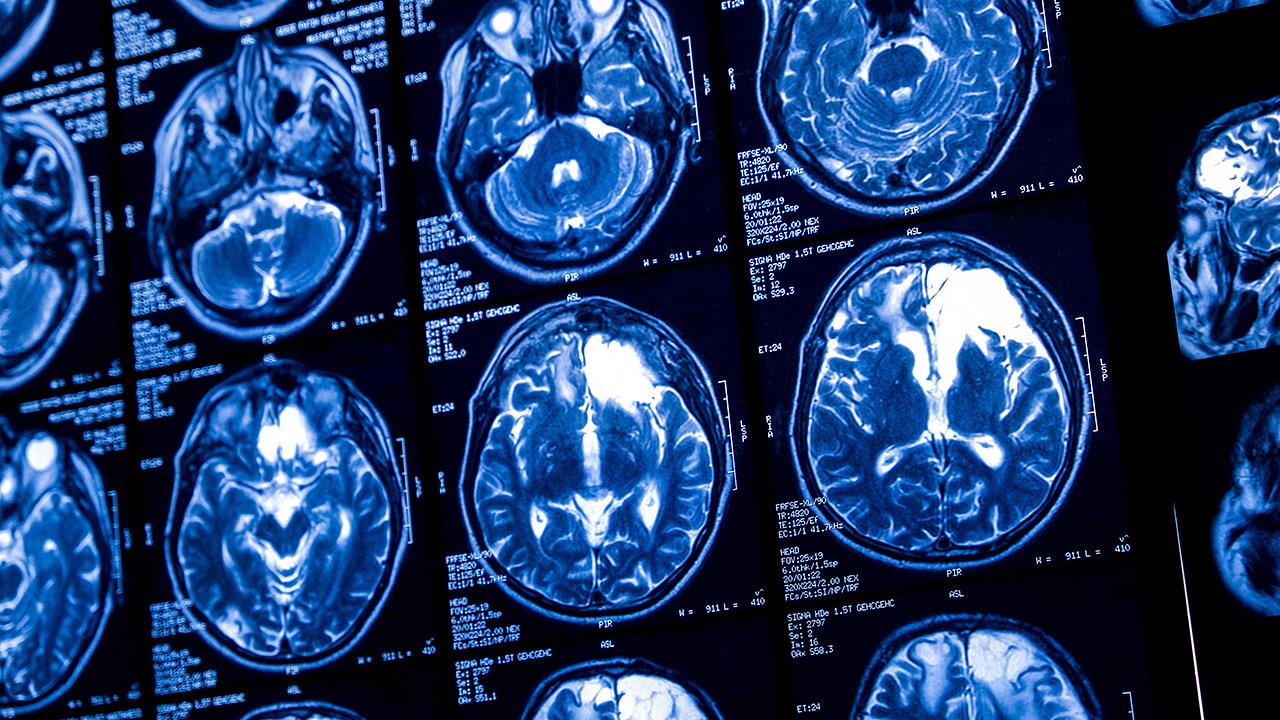

Οι ερευνητές εστίασαν σε στοιχεία 7 ερευνών από την Ευρώπη και τις ΗΠΑ οι οποίες μετρούσαν την καρδιακή λειτουργία  των συμμετεχόντων και χρησιμοποίησαν μαγνητική τομογραφία για την απεικόνιση του εγκεφάλου. Περιελήφθησαν 11.000 άνθρωποι.

Τα αποτελέσματα έδειξαν ότι άνθρωποι με μέτρια έως έντονη συστολική δυσλειτουργία έτειναν να έχουν μικρότερο όγκο εγκεφάλου έναντι αυτών με υγιείς καρδιές.

Επιπλέον, άνθρωποι με διαστολική δυσλειτουργία είχαν μικρότερο όγκο εγκεφάλου -ιδιαίτερα στον ιππόκαμπο. Ακόμα και καρδιακά συμπτώματα που δεν αφορούν πλήρη εμφάνιση καρδιακής ανεπάρκειας συνδέονταν με μικρότερο όγκο εγκεφάλου.